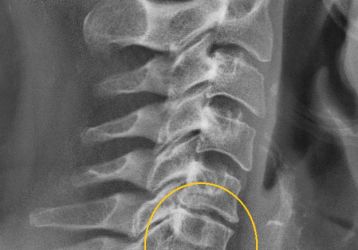

Массаж шеи при остеохондрозе шейного отдела позвоночника: виды, как правильно выполнять

Как правильно выполнять массаж при остеохондрозе шейного отдела позвоночника дома, виды массажей. Показания и противопоказания к применению массажа.